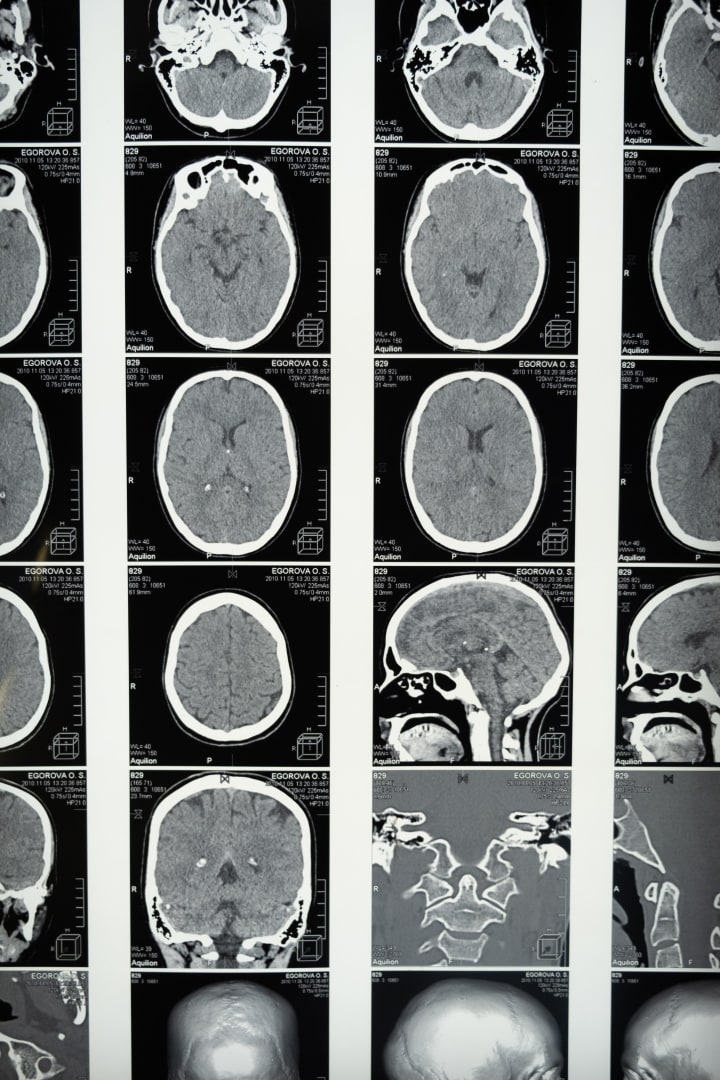

Another area of exploration is the role of inflammation in Alzheimer's. In recent years, studies have shown that chronic inflammation in the brain may contribute to the development and progression of the disease. Researchers are now investigating ways to reduce inflammation and its damaging effects on brain cells, with the aim of developing new therapeutic approaches. Scientists have dedicated extensive research to comprehending the intricacies of Alzheimer's disease by closely examining the plaques and tangles that manifest in the brains of affected individuals. These atypical formations detrimentally impact neural structures, yet the underlying causes and subsequent effects remain elusive. Despite the tireless pursuit of numerous clinical trials, the quest for a definitive cure has yielded minimal success thus far.

2023 has indeed brought a ray of hope. A groundbreaking development has taken place with the approval of Lech Hammerbab by the U.S. Food and Drug Administration. This remarkable drug has been specifically designed to combat amyloid plaques, which are known to be a significant contributor to the progression of Alzheimer's disease. The tireless efforts of pharmaceutical companies, such as Biogen, have been focused on conducting extensive clinical trials for almost two years. Now, with the official approval in 2023, we are one step closer to making this groundbreaking treatment widely accessible to those in need. This remarkable achievement not only signifies a major breakthrough in the field of medicine but also instills a renewed sense of optimism for patients and their loved ones. The future is looking brighter, and we can now envision a world where Alzheimer's is no longer an insurmountable challenge. Collaboration and data sharing among scientists and institutions are also playing a vital role in accelerating progress in Alzheimer's research. By pooling resources and sharing findings, researchers can build upon each other's work and make significant strides toward finding a cure.